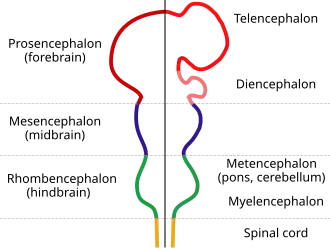

The diencephalon is one of the main vesicles of the brain formed during embryonic development. During the third week of development a neural tube is created from the ectoderm, one of the three primary germ layers, and forms three main vesicles: the prosencephalon, the mesencephalon and the rhombencephalon. The prosencephalon gradually divides into the telencephalon (the cerebrum) and the diencephalon.

Diagram depicting the main subdivisions of the embryonic vertebrate brain. These regions will later differentiate into forebrain, midbrain and hindbrain structures.

Diagram depicting the main subdivisions of the embryonic vertebrate brain. These regions will later differentiate into forebrain, midbrain and hindbrain structures. -